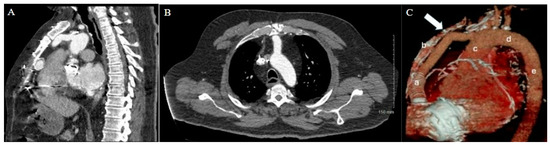

The patient’s history of repeated sternotomies again created a challenging reentry to the thorax. The preoperative CT revealed extensive adhesions between the right atrium and the inferior retrosternal surface with no pericardium present (Figure 4). Due to multiple previous interventions, the patient did not possess adequate peripheral vessels amenable to cannulation. The two-stage sternotomy approach was again utilized to address these adhesions. A partial sternotomy was initiated at the sternal notch and proceeded inferiorly to the third intercostal space, where an inverted T incision was made (Figure 2B). After the partial sternotomy, the aorta and SVC were carefully dissected and directly cannulated, and CPB was initiated. After CPB was initiated, the stepwise sternotomy was completed with the separation of the remaining inferior portion of the sternum. Due to the dense adhesions between the inferior sternum and the right atrium, the atrium was penetrated by the bone saw and the atrial cavity was directly exposed on opening of the chest. Fortunately, the CPB made for a bloodless field, and direct repair of the right atrial wall with a running Prolene suture was easily achieved. The remainder of the heart was dissected, with cardiectomy and transplantation performed according to standard procedure. The sternotomy was left open until the patient underwent OLT on POD1.

Figure 4. Patient 2 CT chest w/contrast. (A) Sagittal view and (B) axial view reveal extensive adhesions between right atrium and inferior retrosternum.

A careful review of the CT imaging was crucial to the preoperative planning of both cases of stepwise sternotomy. The preoperative imaging identified not only structures at risk of reentry injury but also the specific site at which this risk was present. By utilizing landmarks identified in the imaging, we were able to formulate an individualized two-stage approach to reentry that was safe for each patient. With one patient demonstrating inferior retrosternal adhesions and one demonstrating superior retrosternal adhesions, understanding this patient-specific anatomy was necessary to strategize a safe approach to stepwise sternotomy.